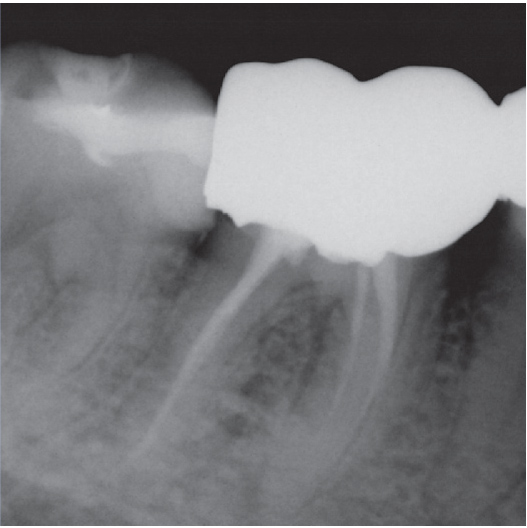

After

After Root Canal treatment